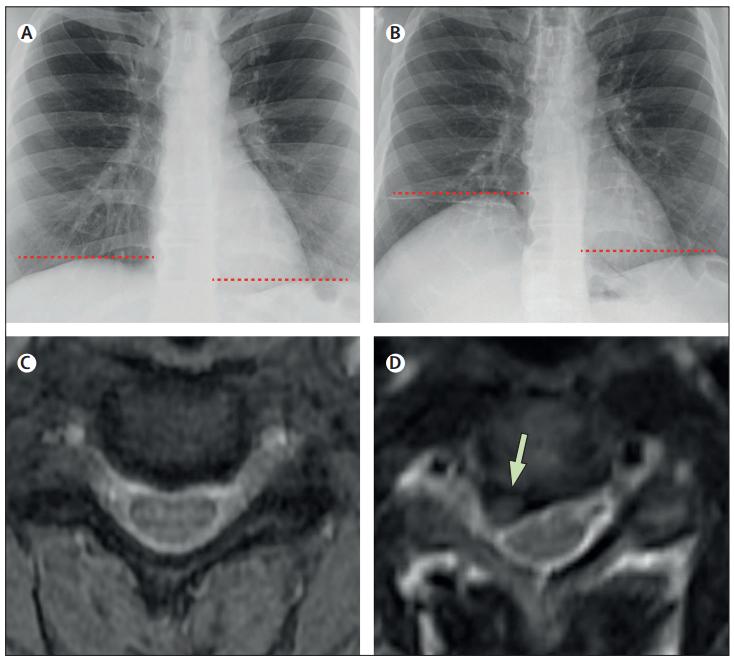

与2年前胸片相比,此次入院胸片提示右侧膈肌异常抬高。颈椎MRI提示C3-4椎间盘向右侧突出,C4神经根严重受压,而2年前MRI显示C3-4椎间盘无突出,根管无狭窄。电诊断测试提示右腕管综合征,但无臂丛神经病变的证据。心电图正常,维生素B12浓度很低 (194 pg/mL),铁浓度(40 μg/dL)。

图:与2年前相比(A),此次入院胸片显示右侧膈肌异常抬高(B)。颈椎MRI显示C3-C4椎间盘突出,伴有严重的右侧C4神经根压迫(箭头, D)。2年前的MRI显示C3-4椎间盘无突出,根管无狭窄(C)。